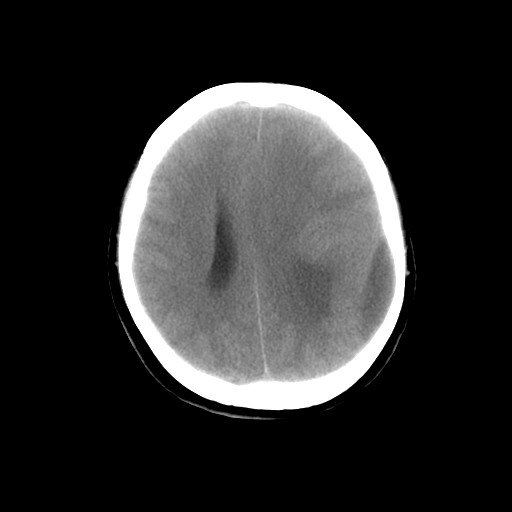

标题: CT14513:女性41岁,头部不适二月余,其它病史不详。请分析 [打印本页]

标题: CT14513:女性41岁,头部不适二月余,其它病史不详。请分析

1.考虑:左侧颞顶叶星形细胞瘤。2.大脑镰下疝。

支持!但楼主所提示处颅骨明显受压变薄,是否有合并蛛网膜囊肿或局部硬膜下水瘤的可能?脑穿通畸形暂不予以考虑:明显占位表现;病侧脑室无扩张;病灶不是较明确的脑脊液密度;边界不清晰。还是mri检查吧,提供的有价值信息更多一些,至少可以排除或肯定蛛网膜囊肿或局部硬膜下水瘤的存在。

1)考虑左侧颞顶叶胶质瘤。2)左侧颞顶部慢性硬膜下血肿?3)大脑镰下疝。